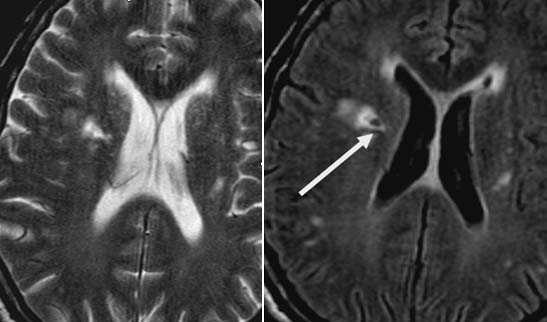

Лакунарное ишемическое ОНМК на фоне хронической сосудистой недостаточности.

Некоторые инфаркты при дисциркуляторной энцефалопатии протекают бессимптомно. Это «немые» инфаркты, которые, как правило, локализуются в глубоких отделах мозга и диагностируются только при МРТ. Этот случай показывает возможности выявление очага ограниченного ишемического ОНМК базальных ядер слева на фоне хронической ишемии.

Выраженная сосудистая энцефалопатия с наличием множественных очагов хронической ишемии, лакунарных постишемических кист. Программа ДВИ четко показывает фокус острого ОНМК в базальных ядрах справа на фоне лейкодистрофии.

Характерным проявлением ДЭП на МР-томограммах является наличие множественных очагов глиоза.

В белом веществе левой лобной и обеих теменных долей, преимущественно субкортикально, выявлены множественные мелкие очаги хронической ишемии (большинство локализованных в бассейне правой средней мозговой артерии).

Проявлением хронической ишемии является также развитие выраженных дистрофических изменений белого вещества паравентрикулярной локализации - лейкоареоз.

Выраженные дистрофические изменения белого вещества паравентрикулярной локализации - лейкоареоз.

Сочетание мультифокальных очаговых изменений с диффузной кортикальной церебральной атрофией.